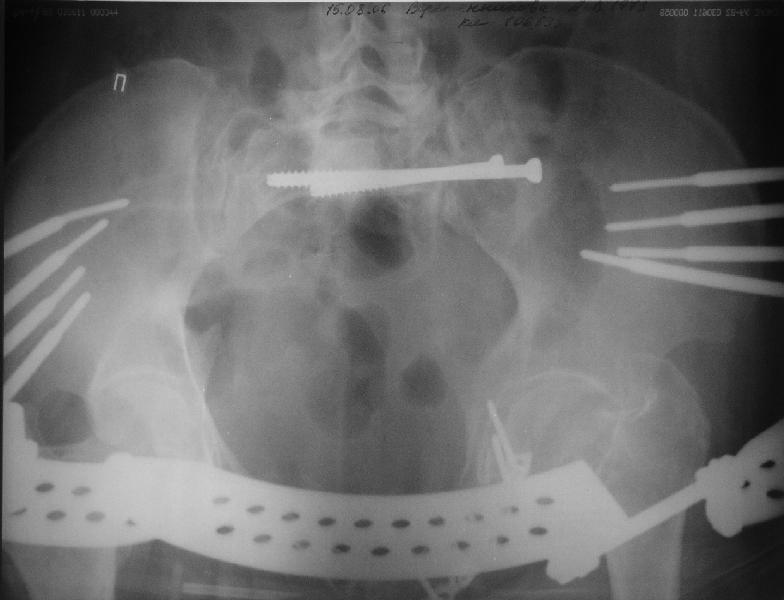

Прооперировали молодую девушку 32 лет спустя 9 мес после травмы. Имелся стойкий болевой синдром, неопороспособность левой н/конечности, моторные и сенсорные нарушения в левой голени и стопе, патологическая подвижность левой половины таза. Первым этапом закрыто в аппарате исправили деформацию ( в течении 2,5 нед). Вторым закрытое введение илиосакральных винтов в крестец (канюллированные 7,2 мм Chm) + туннелизация зоны псевдоартроза спицама Киршнера, реконструкция передних отделов таза, накостный остеосинтез . Аппарат частично демонтирпован, оставлена "передняя рама" После устранения деформации отмечен регресс неврологической симптоматики, уменьшение болевого синдрома. Интересующие вопросы: 1. Прогноз для сращения псевдоартроза крестца. 2. сроки нагрузки весом левой половины таза. Буду очень признателен за ваши мнения по этому поводу.A female 32 y.o. admitted to our unit 9 months after initial injury with pain, inability to bear weight at the left lower limb, sensor and motor disturbances in the left foot and tibia, with mobility of the left hemipelvis.At first closed reduction was performed by an external fixator within 2,5 weeks. After correction her pain decreased and some neurological progress was achieved. Now two iliosacral screws 7,2 mm were inserted, and anterior lesion was fixed by a plate. External fixator was partially unmounted, only anterior frame left in place.Images attached.How would you evaluate chances of healing of the sacrum with the current position?When would you allow weight-bearing of the left leg?THX in advance.